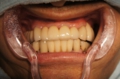

上顎全額的インプラント症例

上の全ての歯がぐらぐらな状態で左上の歯(写真向かって右上)が痛いとご来院。入れ歯は絶対に嫌ということで、まずは痛む左上(レントゲンでは右上)を抜歯、サイナスリフト(骨の移植)を併用しインプラント埋入して残りの歯で無理やり仮歯を支える。左上インプラントが生着し左で咬めるようになったら前歯(鼻の下がくぼんで老人様顔貌を避けるため骨の厚みを出す手術併用)、右上の歯はすべて抜歯して(ソケットリフト併用)しインプラント埋入。生着に時間のかかる日本承認の従来型のインプラントだったので計1年以上の治療期間を要しましたが一度もご自身の歯で咬めない時期はないようにしました。